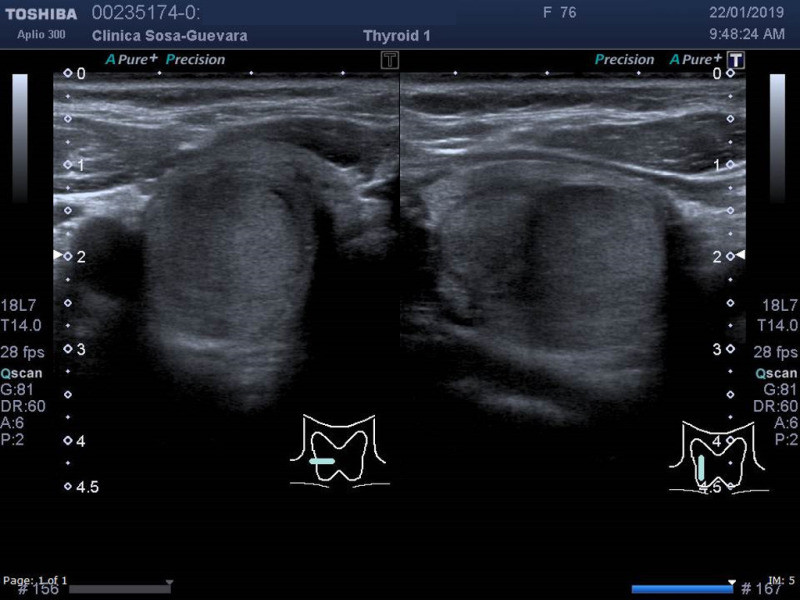

Clínica de Radiología y Ultrasonografía Sosa - Guevara

Ultrasonido de tiroides

Clinicas > Radiologia